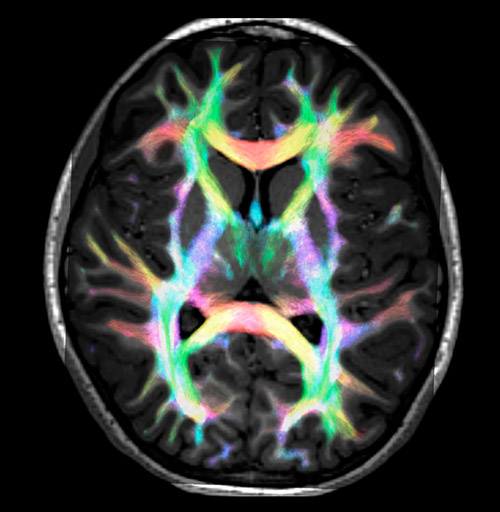

Super-resolution directionally encoded color track-density imaging overlaid on T1-weighted structural MRI.